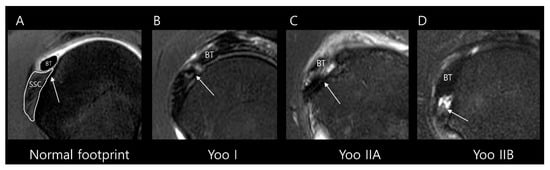

Figure 3.

Subclassification of Lafosse type 1 subscapularis tendon (SSC) partial thickness tears according to the Yoo and Rhee classification. On T2-weighted oblique sagittal images with fat suppression, (A) a normal SSC footprint shows a thin tendinous slip (arrow) in the superior portion, which is closely related to the stability of the biceps tendon (BT). Note that most partial thickness tears (Lafosse type 1) originate from this tendinous slip. (B) Yoo type I tear shows fraying or a longitudinal split at the leading edge (arrow). (C) Yoo type IIA tear is defined as the detachment of less than 50% of the first facet (arrow). (D) Yoo type IIB tear is defined as the detachment of more than 50% of the first facet (arrow).